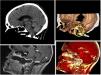

En tomografía computarizada craneal se objetiva perforación a nivel de clivus (flecha blanca). Se amplía estudio con resonancia magnética, objetivándose afectación también de apófisis odontoides (flecha y círculo amarillo) compatible con consumo habitual de cocaína con un absceso asociado que comprime puente y bulbo del mesencéfalo.

Son conocidos los efectos destructivos de la cocaína por la vasoconstricción y necrosis sobre el tabique nasal y el paladar duro, pero no los que puede llegar a provocar sobre la base del cráneo y hasta en vértebras cervicales (fig. 1).